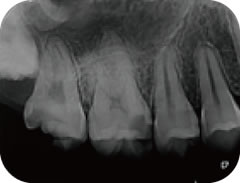

根管治療

歯の中の神経(歯髄)が壊死してしまっているなど、歯髄が残せない場合は根管治療が選択されます。

根管治療とは、歯の内部に入った細菌を除去することによって、痛みや腫れといった症状を取り除く治療のことをいいます。

根管内で増殖した菌を放置すると、歯を支えているあごの骨にまで感染が広がっていきます。さらには根尖性歯周炎という病気に発展し骨が溶けていき、最終的には抜歯するしかなくなります。

こういった事態を避けるために根管治療が必要となります。

根管治療はとても繊細で、高度な技術が求められる治療です。

髙橋歯科では、細菌の感染などに細心の注意をはらい患者様が満足できる根管治療を提供しています。